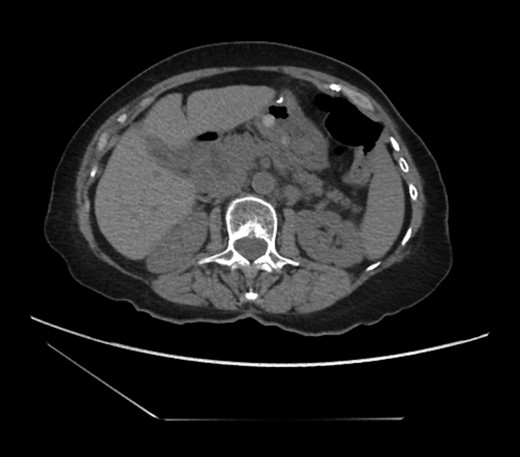

Diagnosing an internal hernia is frequently accomplished using physical exam and CT imaging. Abdominal X-ray does have some nonspecific findings suggestive of internal hernia but is usually inadequate for diagnosis. Diagnosis of a foramen of Winslow hernia, however, is only accomplished in 10% of patients preoperatively [3]. As previously mentioned this diagnosis is rare and often presents with vague obstructive type symptoms. This likely contributes to the low occurrence of accurate preoperative diagnosis. However, several radiographic findings were seen in this patient that suggested a foramen of Winslow hernia preoperatively. First, there is visible swirling of the mesentery on the CT scan that is indicative of internal hernia (Fig. 1). Second, there are loops of small bowel that can be visualized between the IVC and the edge of the liver in a supra renal position along the lesser curvature of the stomach (Figs 1 and 2). When compared to a CT of the abdomen and pelvis obtained 4 years prior to presentation, there is actually evidence that this patient had a non-obstructing foramen of Winslow hernia at that time as demonstrated by bowel being visualized in the lesser sack (Fig. 5). These findings, especially small bowel along the lesser curvature of the stomach, are inconsistent with normal anatomy and strongly indicative a foramen of Winslow hernia.

CT abdomen and pelvis coronal view of foramen of Winslow hernia.